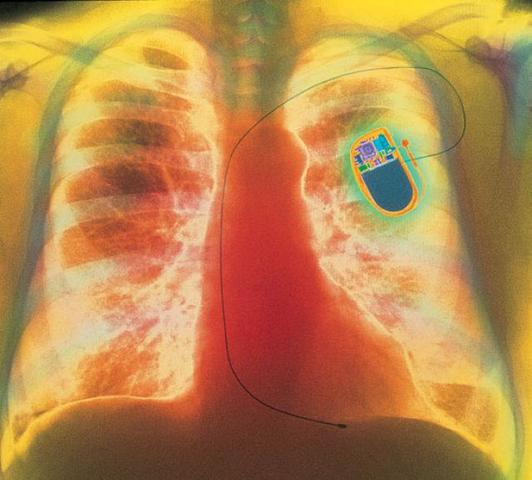

• El Marcapasos (Año 1958)

El Marcapasos (Año 1958)

tener un defecto cardiaco irreversible implicaba la muerte segura. Esto cambió cuando los médicos suecos Rune Elmqvist y Ake Senning diseñaron el primer marcapasos implantable en 1958. Sin embargo, el instrumento falló a las pocas horas de puesto en marcha y fue el ingeniero norteamericano Wilson Greatbatch quien perfeccionó el invento. Probó el prototipo en un perro en el mismo año y, en 1960, Henry Hannafield, de 77 años, se convirtió en el primer ser humano en recibir el implante.